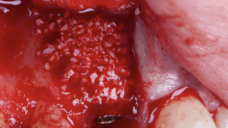

Given the significant buccal defect, guided bone regeneration (GBR) was performed simultaneously. A mixture of autologous bone and creos™ xenogain™ was applied to the defect and covered with a resorbable creos™ membrane to restore ridge width and support the buccal contour. In addition, a connective tissue graft was harvested and placed in the vestibular region to increase the thickness of keratinized mucosa. This combined approach addressed both hard and soft tissue deficiencies, providing the biological foundation for a stable and esthetic outcome.